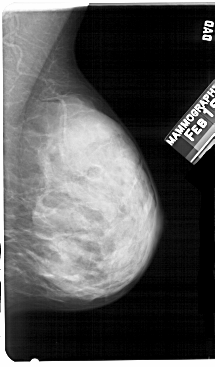

A_1326_1.LEFT_MLO

LEFT_MLO LINES 5491 PIXELS_PER_LINE 3166 BITS_PER_PIXEL 12 RESOLUTION 43.5 OVERLAY